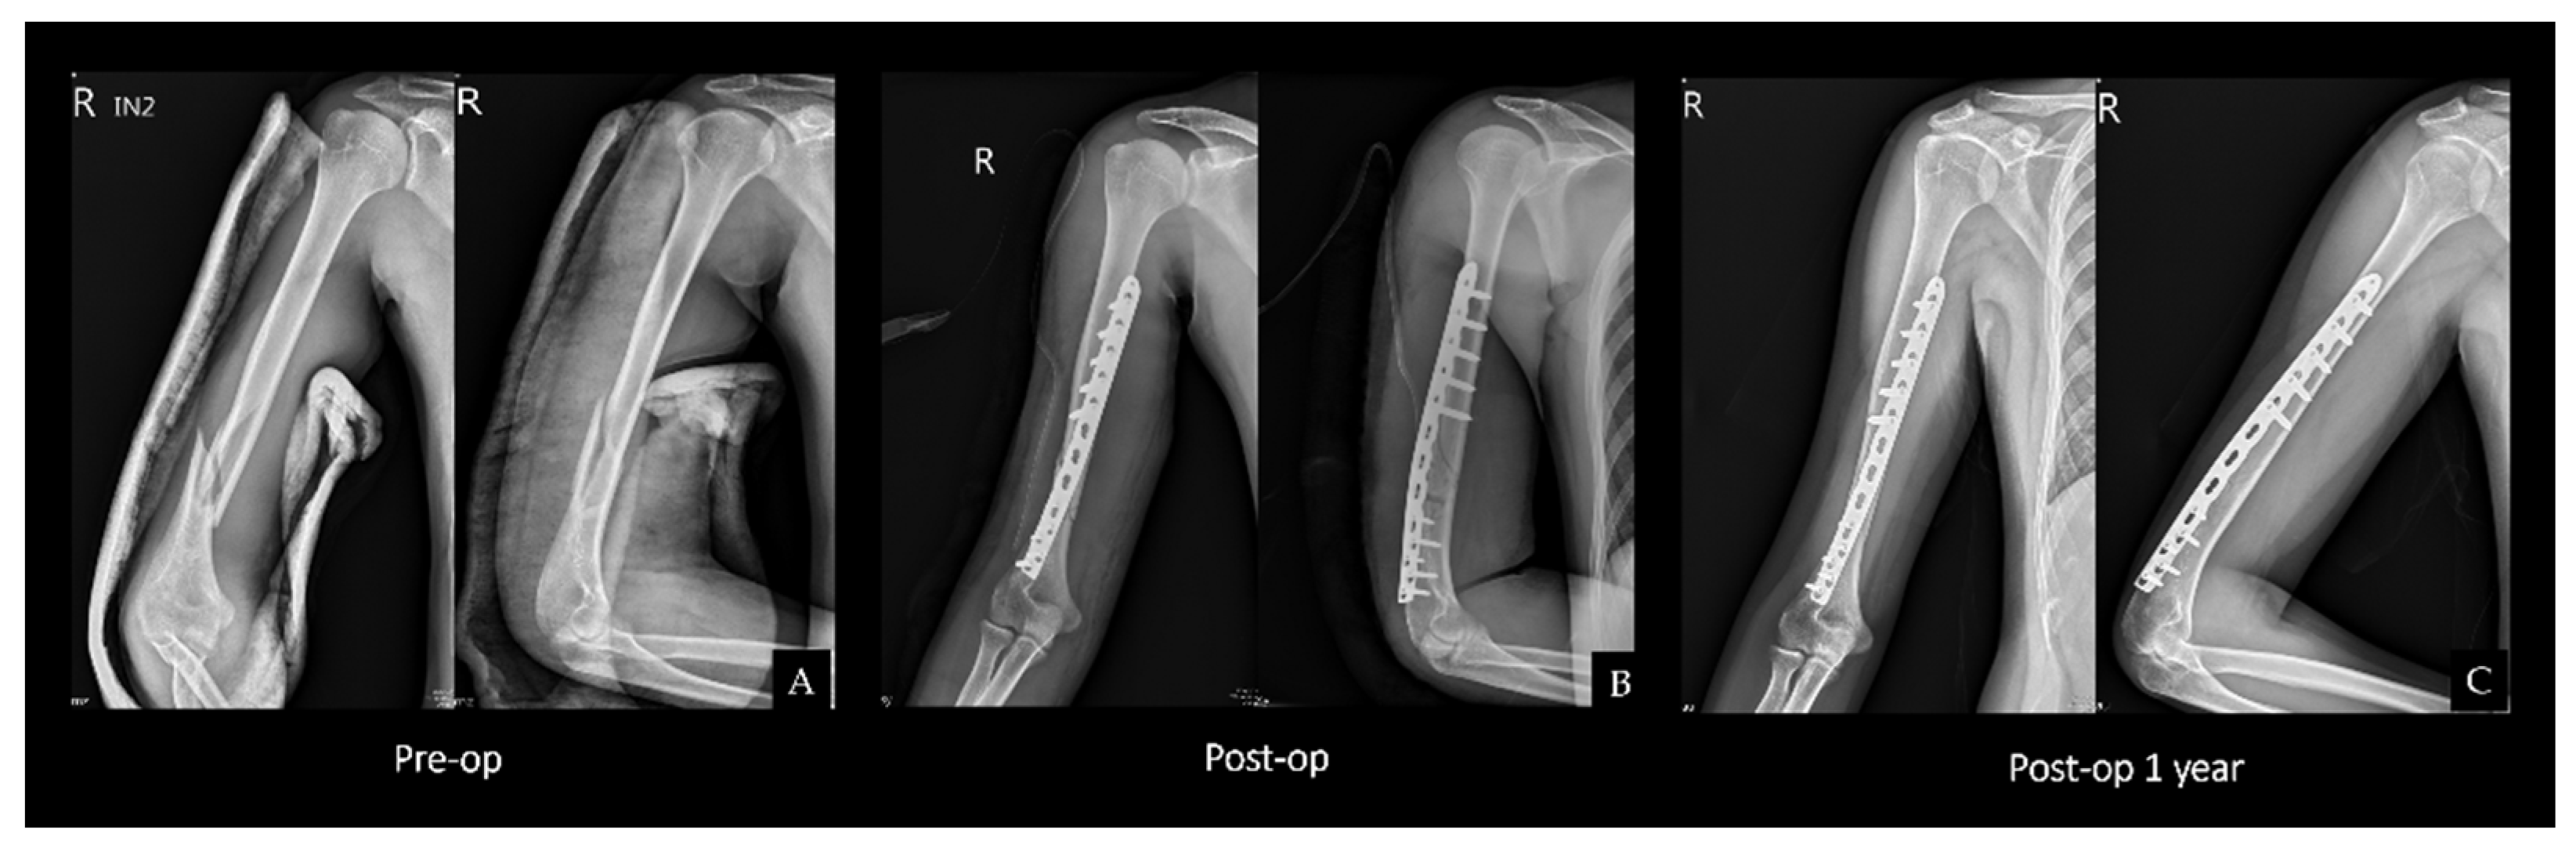

2.2. Surgical Technique

2.3. Double Plating

2.4. Single Plating